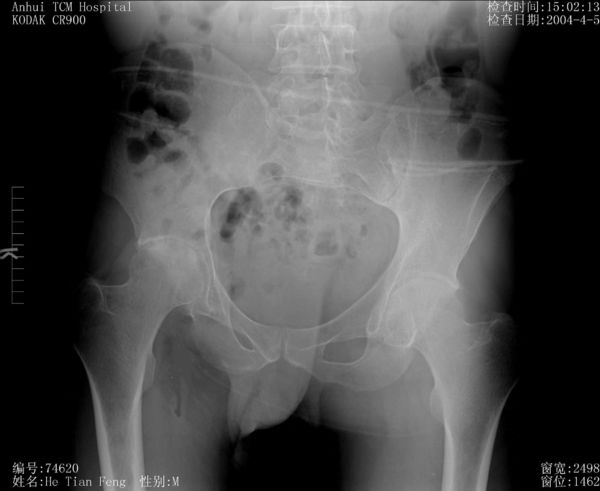

周章武:类风湿性关节炎髋关节X片表现

类风湿性关节炎是一种自身免疫系统病,也常常影响到髋关节,出现髋关节的类风湿性关节炎。

图 类风湿性关节炎髋关节X片表现

推荐医院:安徽省中医院 http://www.91160.com/unit/show/uid-100014603.html

推荐医生:周章武 http://www.91160.com/doc/show/depid-100091007/docid-100219005.html